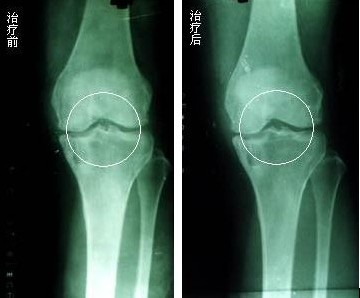

“针刀松解术”是运用中医的精华结合西医理念,该疗法将直径0.8毫米的“小针刀”,迅速刺入患者疼痛关节处穴位,只需短短几秒就可将针刀刺入病灶,产生机械的刺激,松解软组织的粘连、挛缩和瘢痕,改善膝关节周围血运,促进血液回流,恢复关节周围软组织力学平衡,从而有利于骨关节自体修复。在诊断明确、定位精确的基础上,施“针刀松解术”,剥离、切割松解病变软组织的粘连、挛缩、结疤处,能有效解除这些引起动态平衡的病理因素,恢复软组织的动态平衡和生物力学平衡。并结合药物离子熏蒸技术把特制药物以离子形态经透皮吸收直达病灶,产生杀菌、消炎、止痒、治痛等作用,双管齐下,标本兼治,疗效显着。

因此骨性关节炎的治疗关键在于保持关节的一定活动幅度,增强受累关节周围肌肉张力,增加关节的稳定性,并能大限度地延缓关节老化,保持一个年轻健康的关节。而“针刀松解术”就是针对这几点而研究出来的。

“针刀松解术”能迅速刺入患者疼痛关节处穴位,只需短短几秒就可将针刀刺入病灶,产生机械的刺激,松解软组织的粘连、挛缩和瘢痕,改善膝关节周围血运,促进血液回流,恢复关节周围软组织力学平衡,从而有利于骨关节自体修复。相对于骨性关节病患者来说,一个好的骨性关节病治疗方法,是能够让患者减少很多病痛,这样同样也能节省不少的金钱。而这种“针刀松解术”的治疗优势就恰恰在于此,不仅疗程短,费用还低。其优势如下: